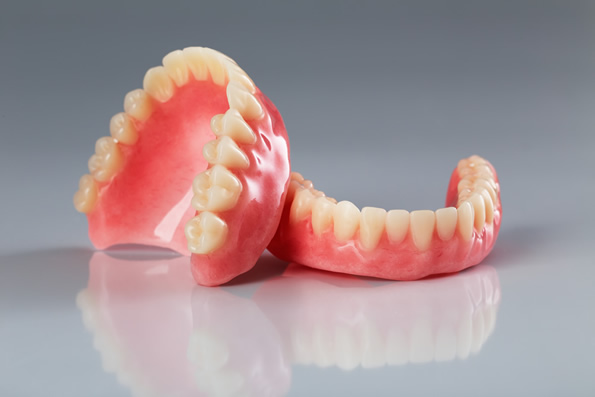

Próteses Total

Conhecidas também como Dentaduras, são próteses removíveis, indicadas para pacientes que perderam todos os dentes da arcada superior e/ou inferior. São confeccionadas através de moldagens que reproduz a anatomia da mucosa da arcada do indivíduo. Este método de tratamento relativamente rápido é também de baixo custo e capaz de devolver estética, e função mesmo sendo removível e apenas suportada pela mucosa oral.